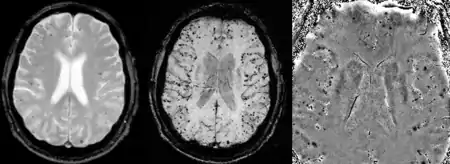

Cerebral amyloid angiopathy can be presented with lobar intracerebral hemorrhage or microbleeds in the brain. The bleeding usually occurs on the surfaces of the brain in contrast with intracranial haemorrhage due to high blood pressure which occurs deep locations of the brain such as basal ganglia and pons. In lobar intracerebral bleed, computed tomography (CT) scan would show hyperdense haemorrhage area and hypodense odema around the haemorrhagic site.[17]

MRI sequence of gradient echo and Susceptibility weighted imaging(SWI) are useful in detecting microbleeds and deposition of iron on the brain cortex (cortical superficial siderosis).[17] Other MRI indicators of CAA include white matter hyperintensities and cortical thinning.[29]